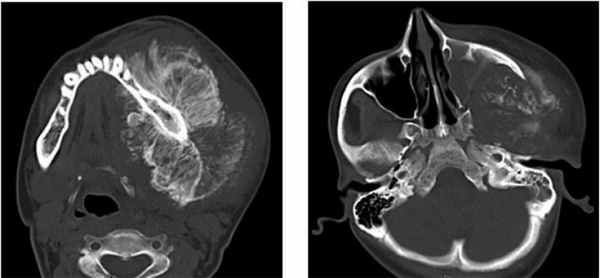

Пациент муж., 50 лет, в анамнезе операция удаления амелобластомы в пределах видимо здоровых тканей. Обратился с жалобами на повторное развитие опухолеподобного образования (Рис. 4).

Рис. 4. КТ свидетельствует о рецидиве кистозной формы амелобластомы.

Поражено тело нижней челюсти больше справа, определяется «вздутие» и неравномерное истончение передней пластины тела челюстной кости, обширный участок деструкции с четкими, полицикличными контурами, неправильной овальной формы, размерами 4,5 х 3,5 х 3,0 см. Кортикальный слой передней поверхности челюсти значительно истончен, местами не определяется, периостальная реакция отсутствует. В патологически измененном участке видны перегородки и известковые включения. Правое ментальное отверстие и дистальный отдел канала правого нижнеальвеолярного нерва не определяется.

Клинический случай №4

Пациент муж., 32 года (Рис. 5).

Рис. 5. КТ свидетельствует об объемном образовании нижней челюсти, требующем верификации.

Поражена правая ветвь нижней челюсти. Определяется объемное кистозное образование, овальной формы с четкими полицикличными контурами, замещающее весь венечный отросток и распространяющееся на суставной отросток. Объем кости увеличен за счет вздутия. Кортикальный слой значительно истончен, местами не прослеживается. Канал нижнеальвеолярного нерва вплотную прилежит к образованию, верхняя его стенка в проксимальном отделе не прослеживается. В подьязычной области справа виден лимфоузел, размерами 1,7 на 0,9 см.